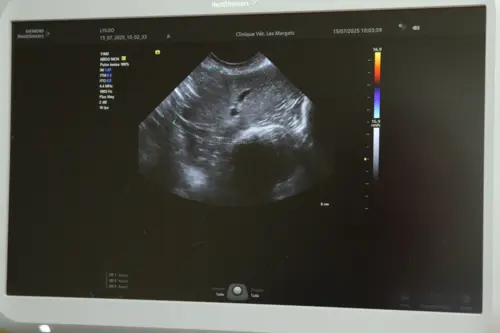

L’échographie est un outil que nous utilisons de plus en plus en simple consultation pour visualiser ce qui se passe à l’intérieur de l’organisme de votre animal (abdomen, cœur…). Indolore, sans danger et rapide à mettre en œuvre, l’échographie fait incontestablement partie des progrès les plus utiles de la médecine vétérinaire de ces dernières années. Nous possédons deux appareils :

- un appareil portable et ergonomique qui nous procure des échographies conventionnelles de très haute définition. Il est utilisé en consultation, en urgence ou même à domcile

- un appareil de dernière génération (SIEMENS ACUSON JUNIPER), équipé de 3 sondes (linéaire, microconvexe, et "phase array") et du Doppler-couleur qui améliore de manière exceptionnelle la qualité de nos diagnostics échographiques.